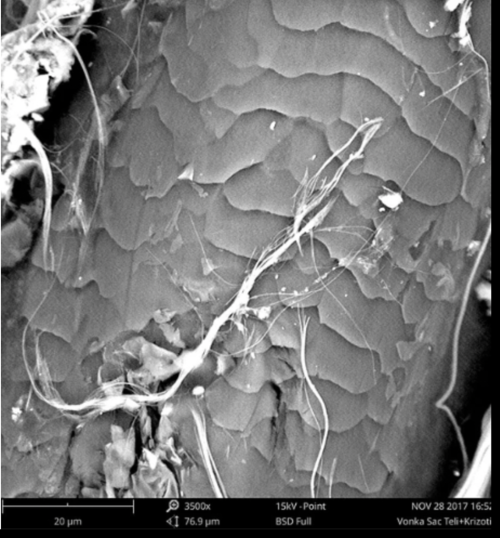

4- Elektron mikroskopide Saç teli üzerinde krizotil asbest